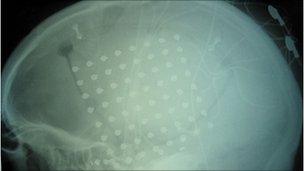

In a surgical procedure, a plastic pad containing a number of electrodes is implanted under the skull.

The study also showed that the large-area arrays utilised for the epilepsy research would not be necessary for future electrocorticography implants; an area just 4mm by 4mm can provide the same level of information.